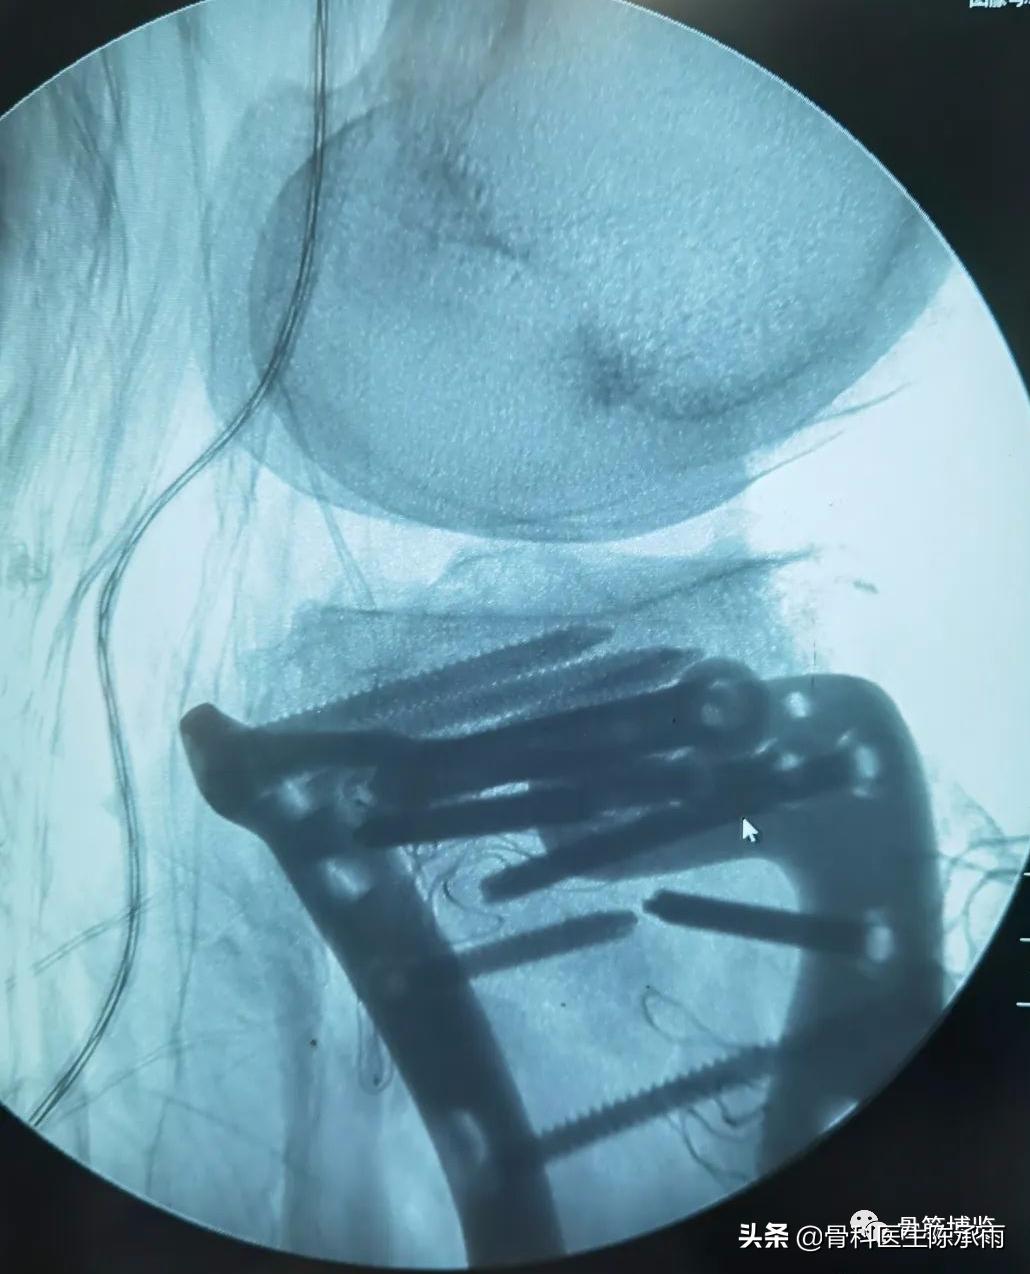

这2例患者皮肤条件差,全身多发骨折,小腿皮肤条件差,1例筋膜高压切开,1例整个小腿布满张力性水泡,胫骨骨折都在伤后30天才能手术。

下例胫平台骨折皮肤条件差,内侧板取两端小切口置入内板固定。胫骨结节处撕脱骨折以1枚拉力螺钉固定。